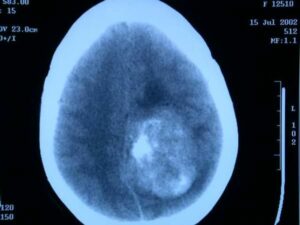

El programa de detecció precoç de càncer de mama a Catalunya detecta més de 1.200 tumors, molts en fase inicial

El càncer de mama, en les dones, és el més freqüent arreu del món. S’estima [...]